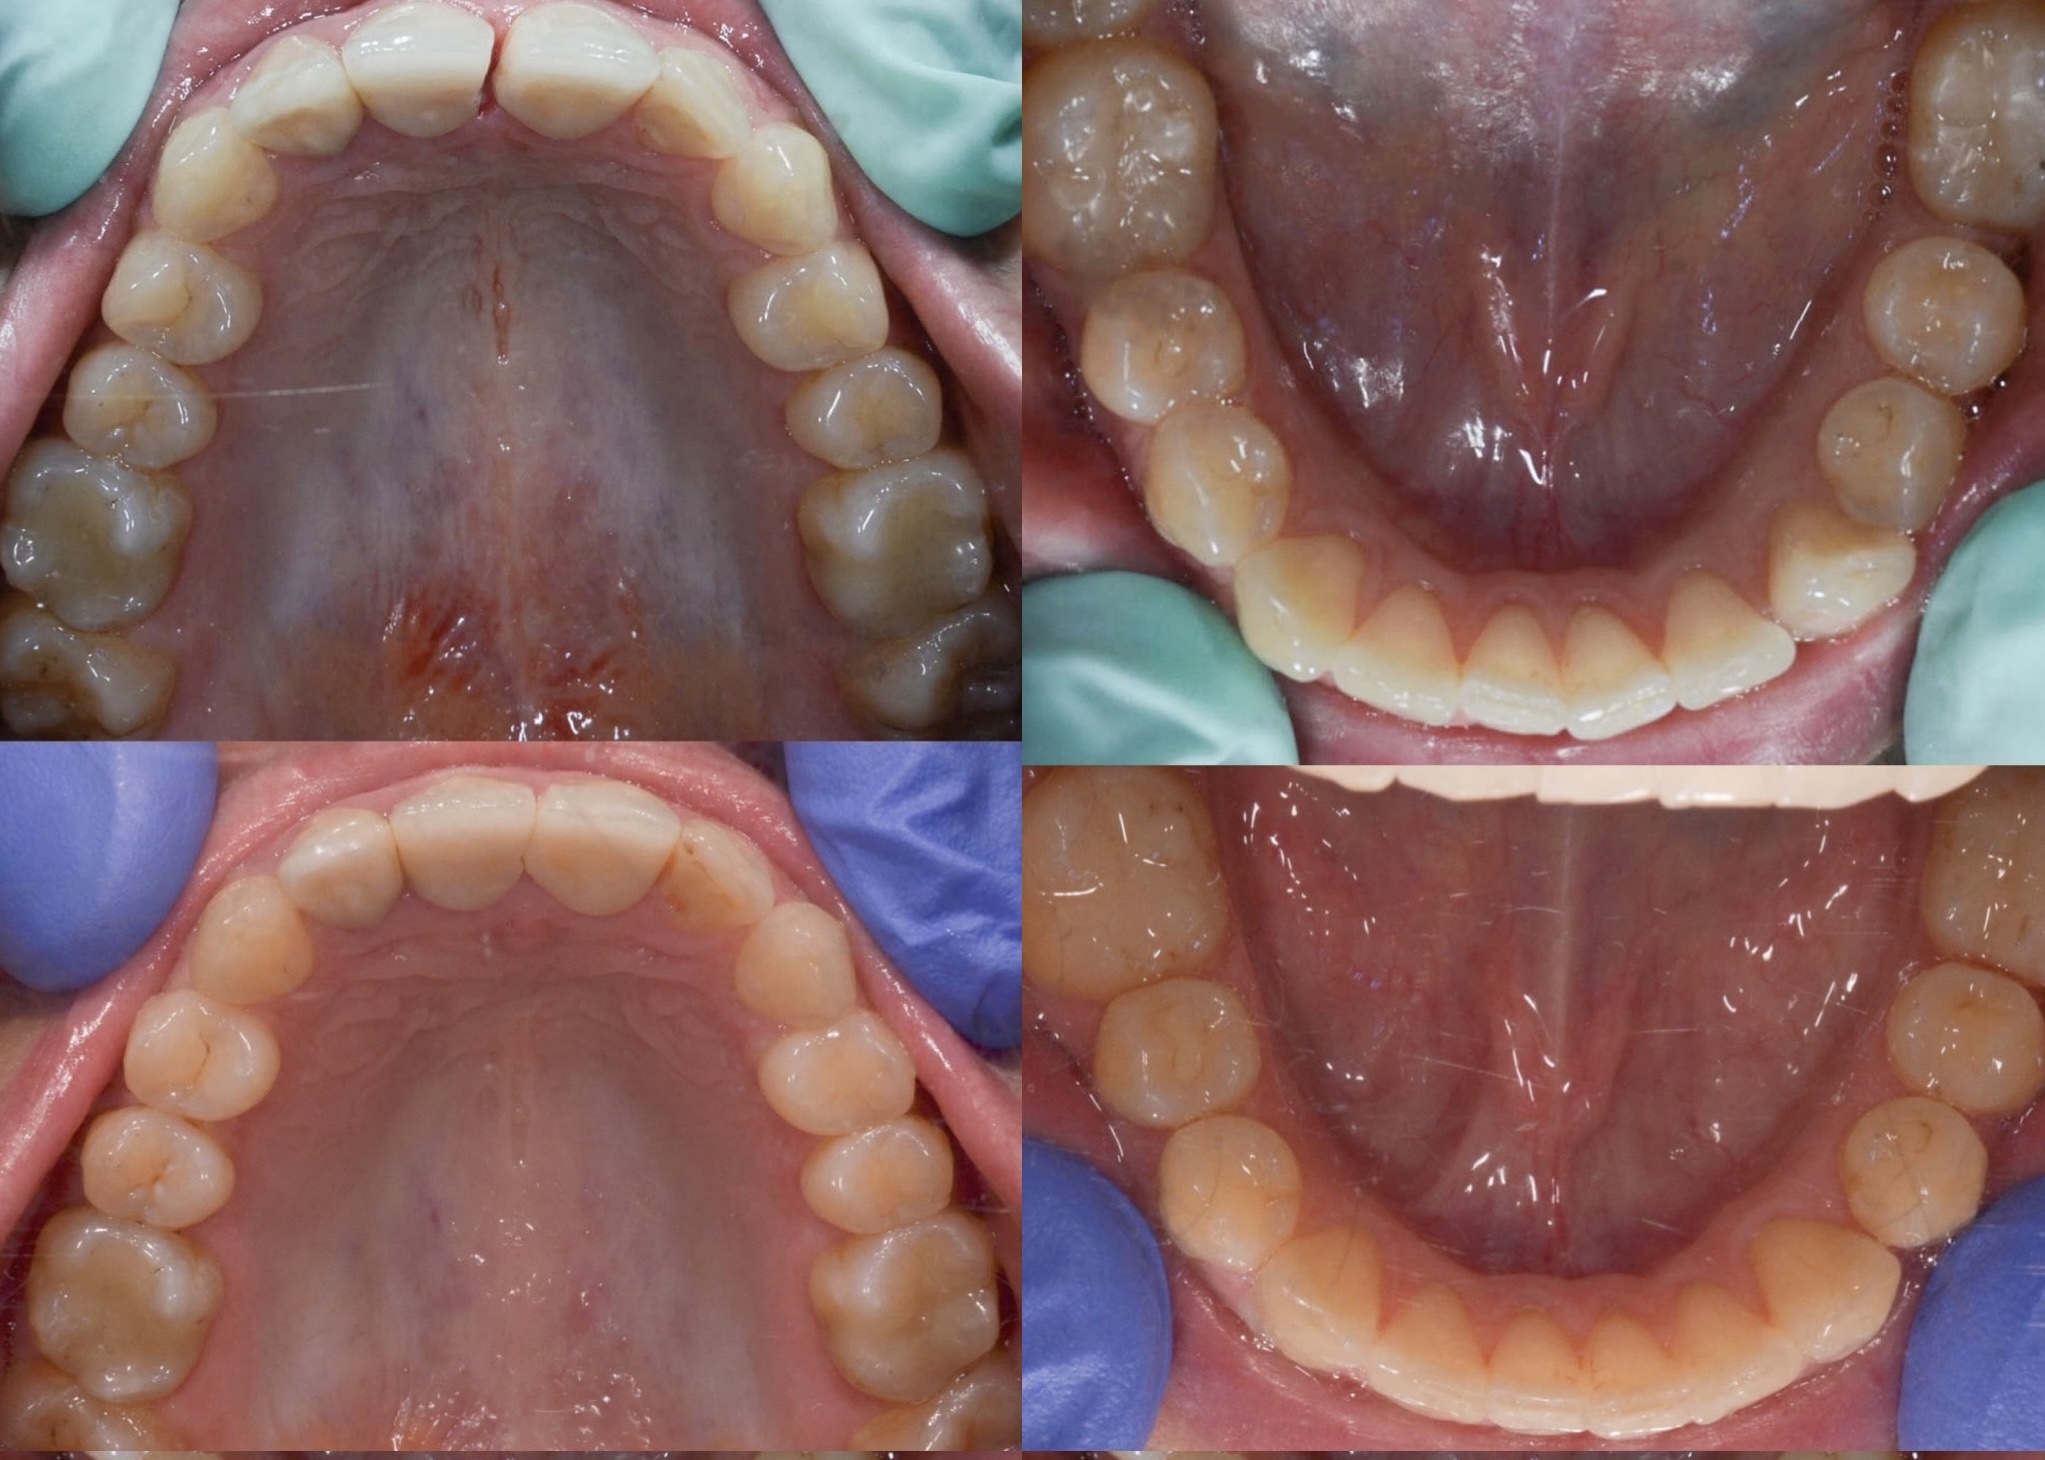

U galeriji slika su prikazani klinički slučajevi ovakvih odraslih pacijenta bilo da se radi samo o ortodontskoj terapiji ili predprotetskoj ortodonciji.

Kompresija –fiksni aparat bez ekstrakcije zuba

Slučaj 1